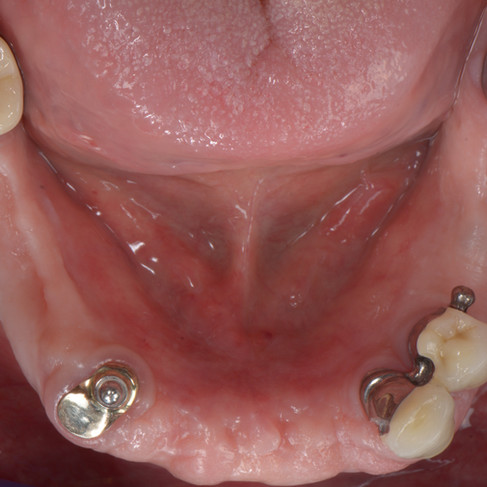

Vorher-Nachher Beispiele aus der Praxis